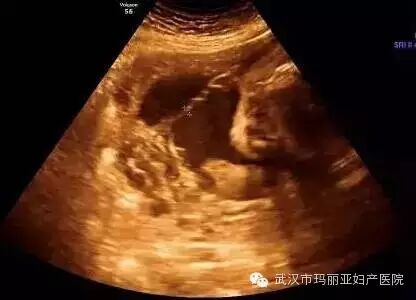

武汉玛丽亚妇产医院引进的世界领先的美国GE-E8四维彩超设备室目前世界上最先进、分辨率最高的彩色超声设备,具有即时立体成像、清晰准确的特点。

它能够多方位、多角度地观察宫内胎儿的生长发育情况,为早期诊断胎儿先天性体表畸形和发育异常提供科学依据。还能对胎儿的体表进行检查,如唇裂、脊柱裂、大脑、肾、 骨骼发育不良等,以便尽早的进行治疗。